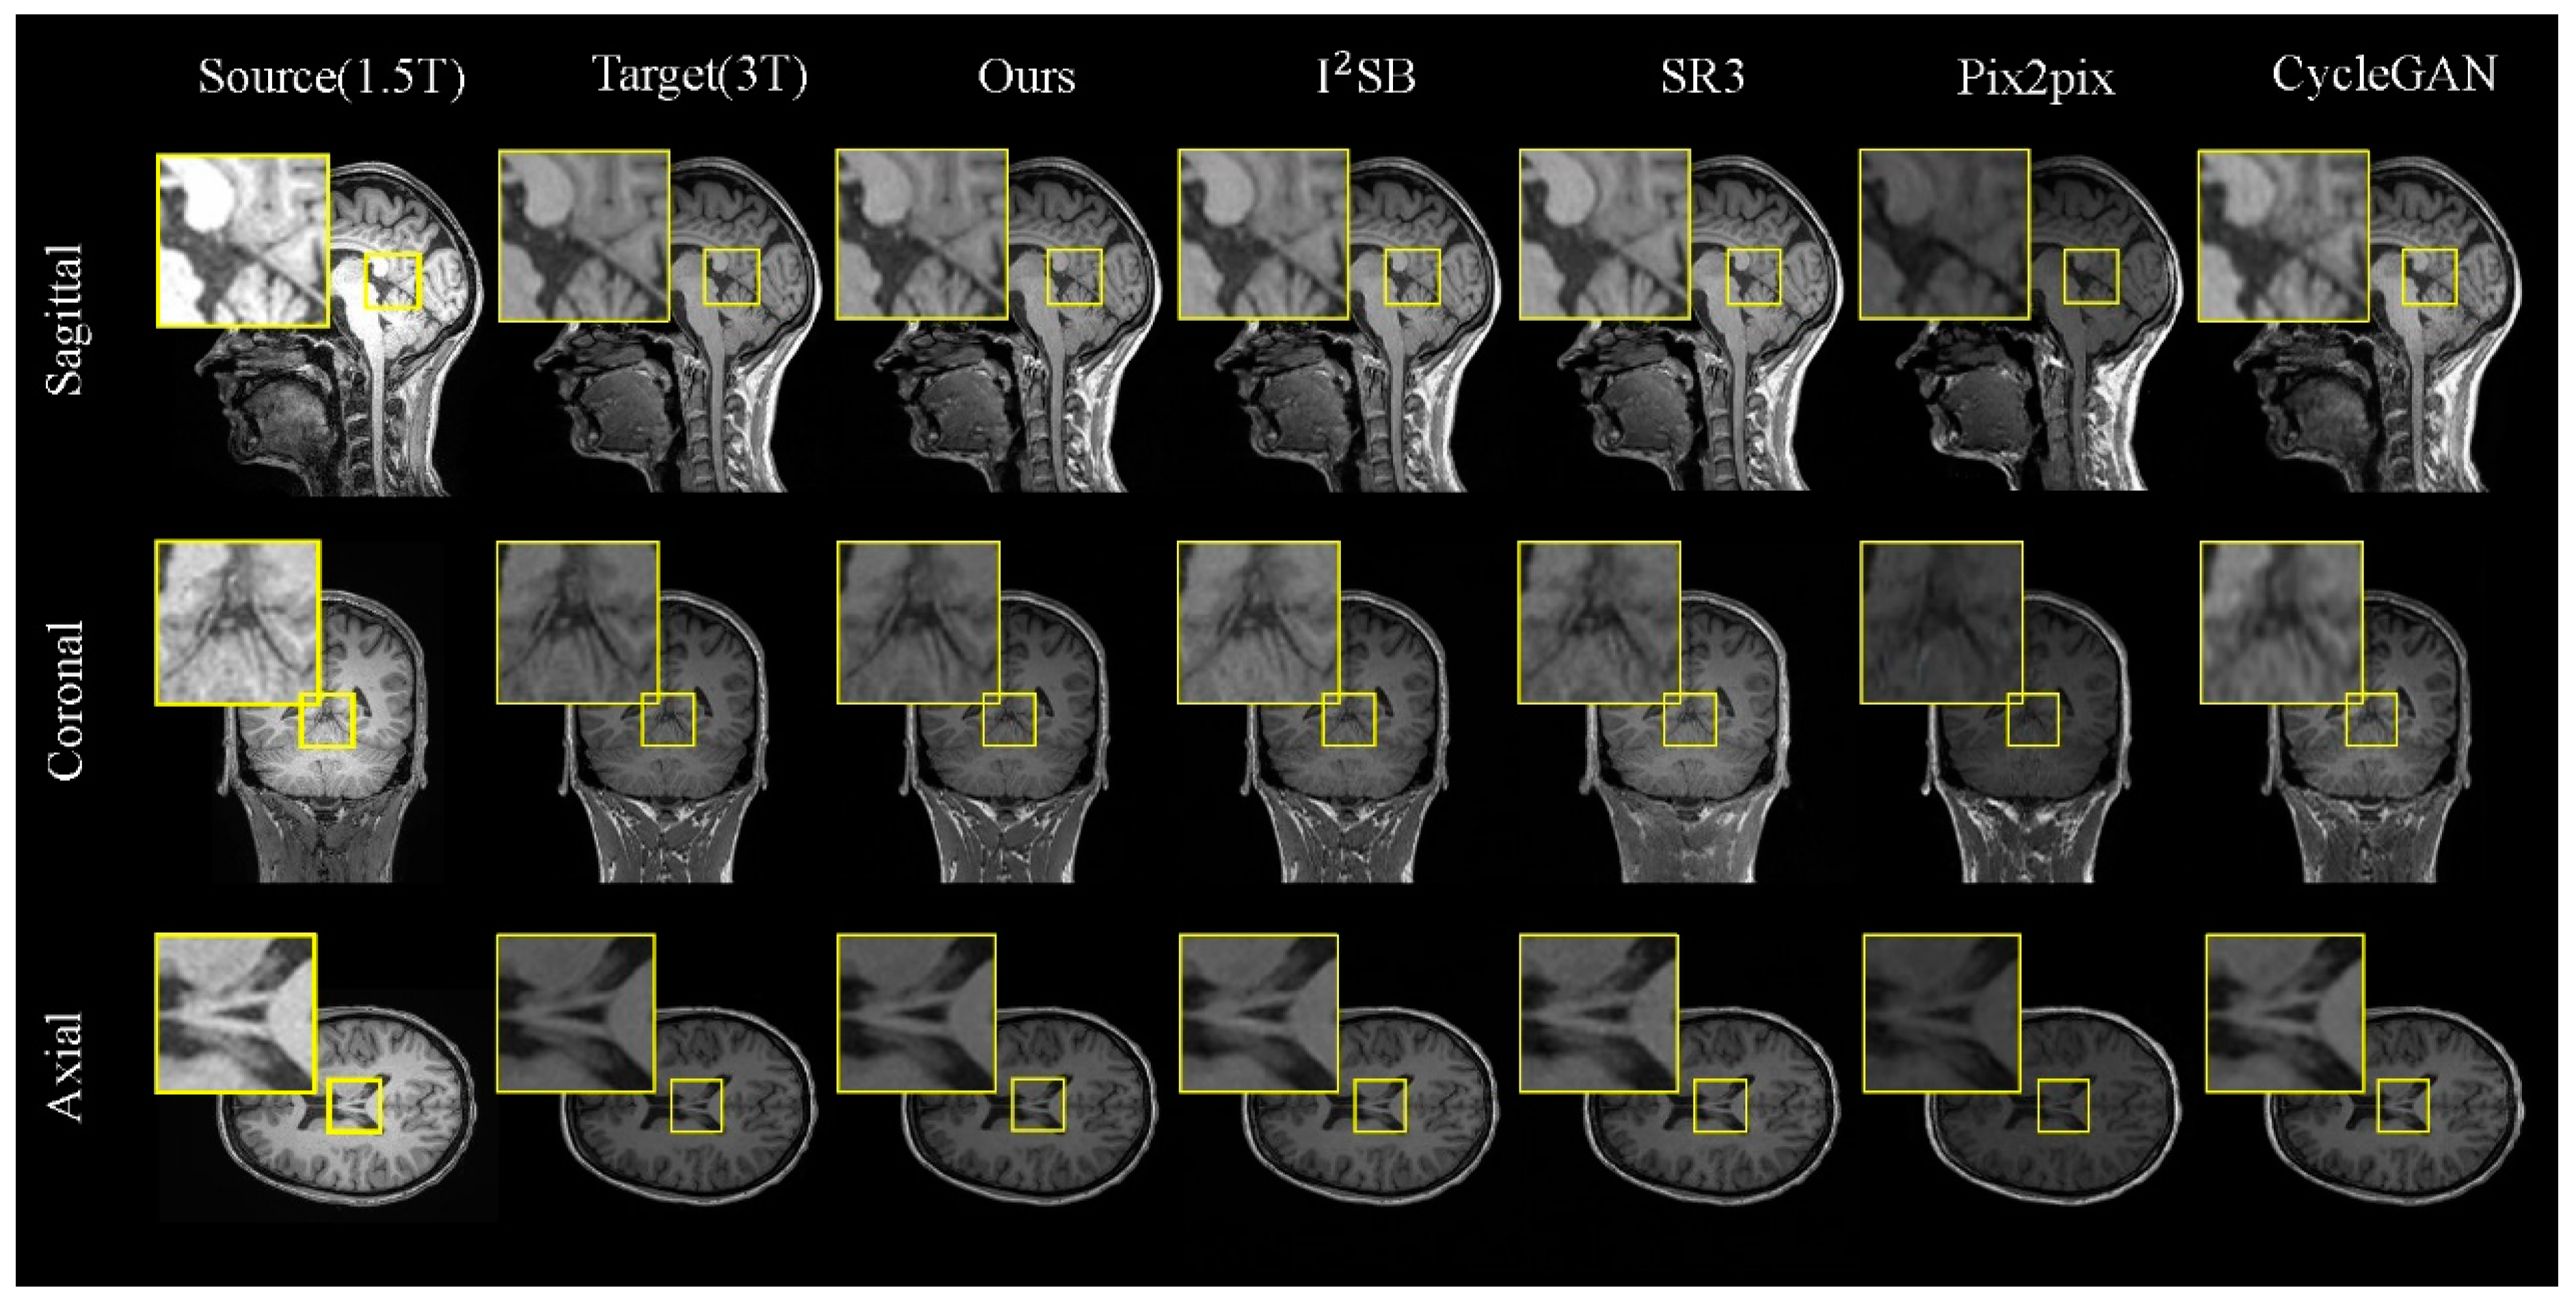

Results on the 1.5T–3T Dataset. Table 1 presents a comparative analysis of various methods on the 1.5T–3T test set, showcasing both the quantitative results and the visual outcomes for the 1.5T and 3T MRI images (as illustrated in Figure 5). For a detailed analysis, we selected local regions in three directions for magnified display (indicated by the yellow box).

In Figure 5, we observe that our model excels in generating tasks across the sagittal, coronal, and axial planes. When comparing different brain regions in the slices, although CycleGAN and Pix2pix can reproduce the overall brain morphology similar to the real images, their outputs exhibit significant discrepancies in finer details. The diffusion-based models, I2SB and SR3, perform better in preserving brain structural information but still fall short in capturing detailed tissue features. In contrast, the FADM excels in capturing tissue details and texture features, particularly in the sagittal and coronal plane generation tasks, where it significantly outperforms other methods. In the axial plane generation task, where the brain structures in MRI images are relatively simpler, the FADM’s results are comparable to those of I2SB.

The quantitative results in Table 1 further corroborate the FADM’s superiority. Our model demonstrates significant improvements in the PSNR, SSIM, and FID scores, especially in the sagittal and coronal plane generation tasks, where the FADM exhibits higher PSNR and SSIM scores and lower FID values, indicating higher image quality and better stability. These findings suggest that the FADM can be effectively utilized to generate high-quality 3T MRI images from 1.5T MRI images when the direct acquisition of 3T MRI images is challenging.

Figure 5. Comparisons of 2D slices (axial, coronal, and sagittal views) generated by our FADM and I2SB [19], SR3 [18], Pix2pix [22], and CycleGAN [23] based on our 1.5T–3T test set. Yellow boxes highlight the central region where the FADM produces more detailed and sharper textures, whereas other methods yield artifacts or blurry effects.